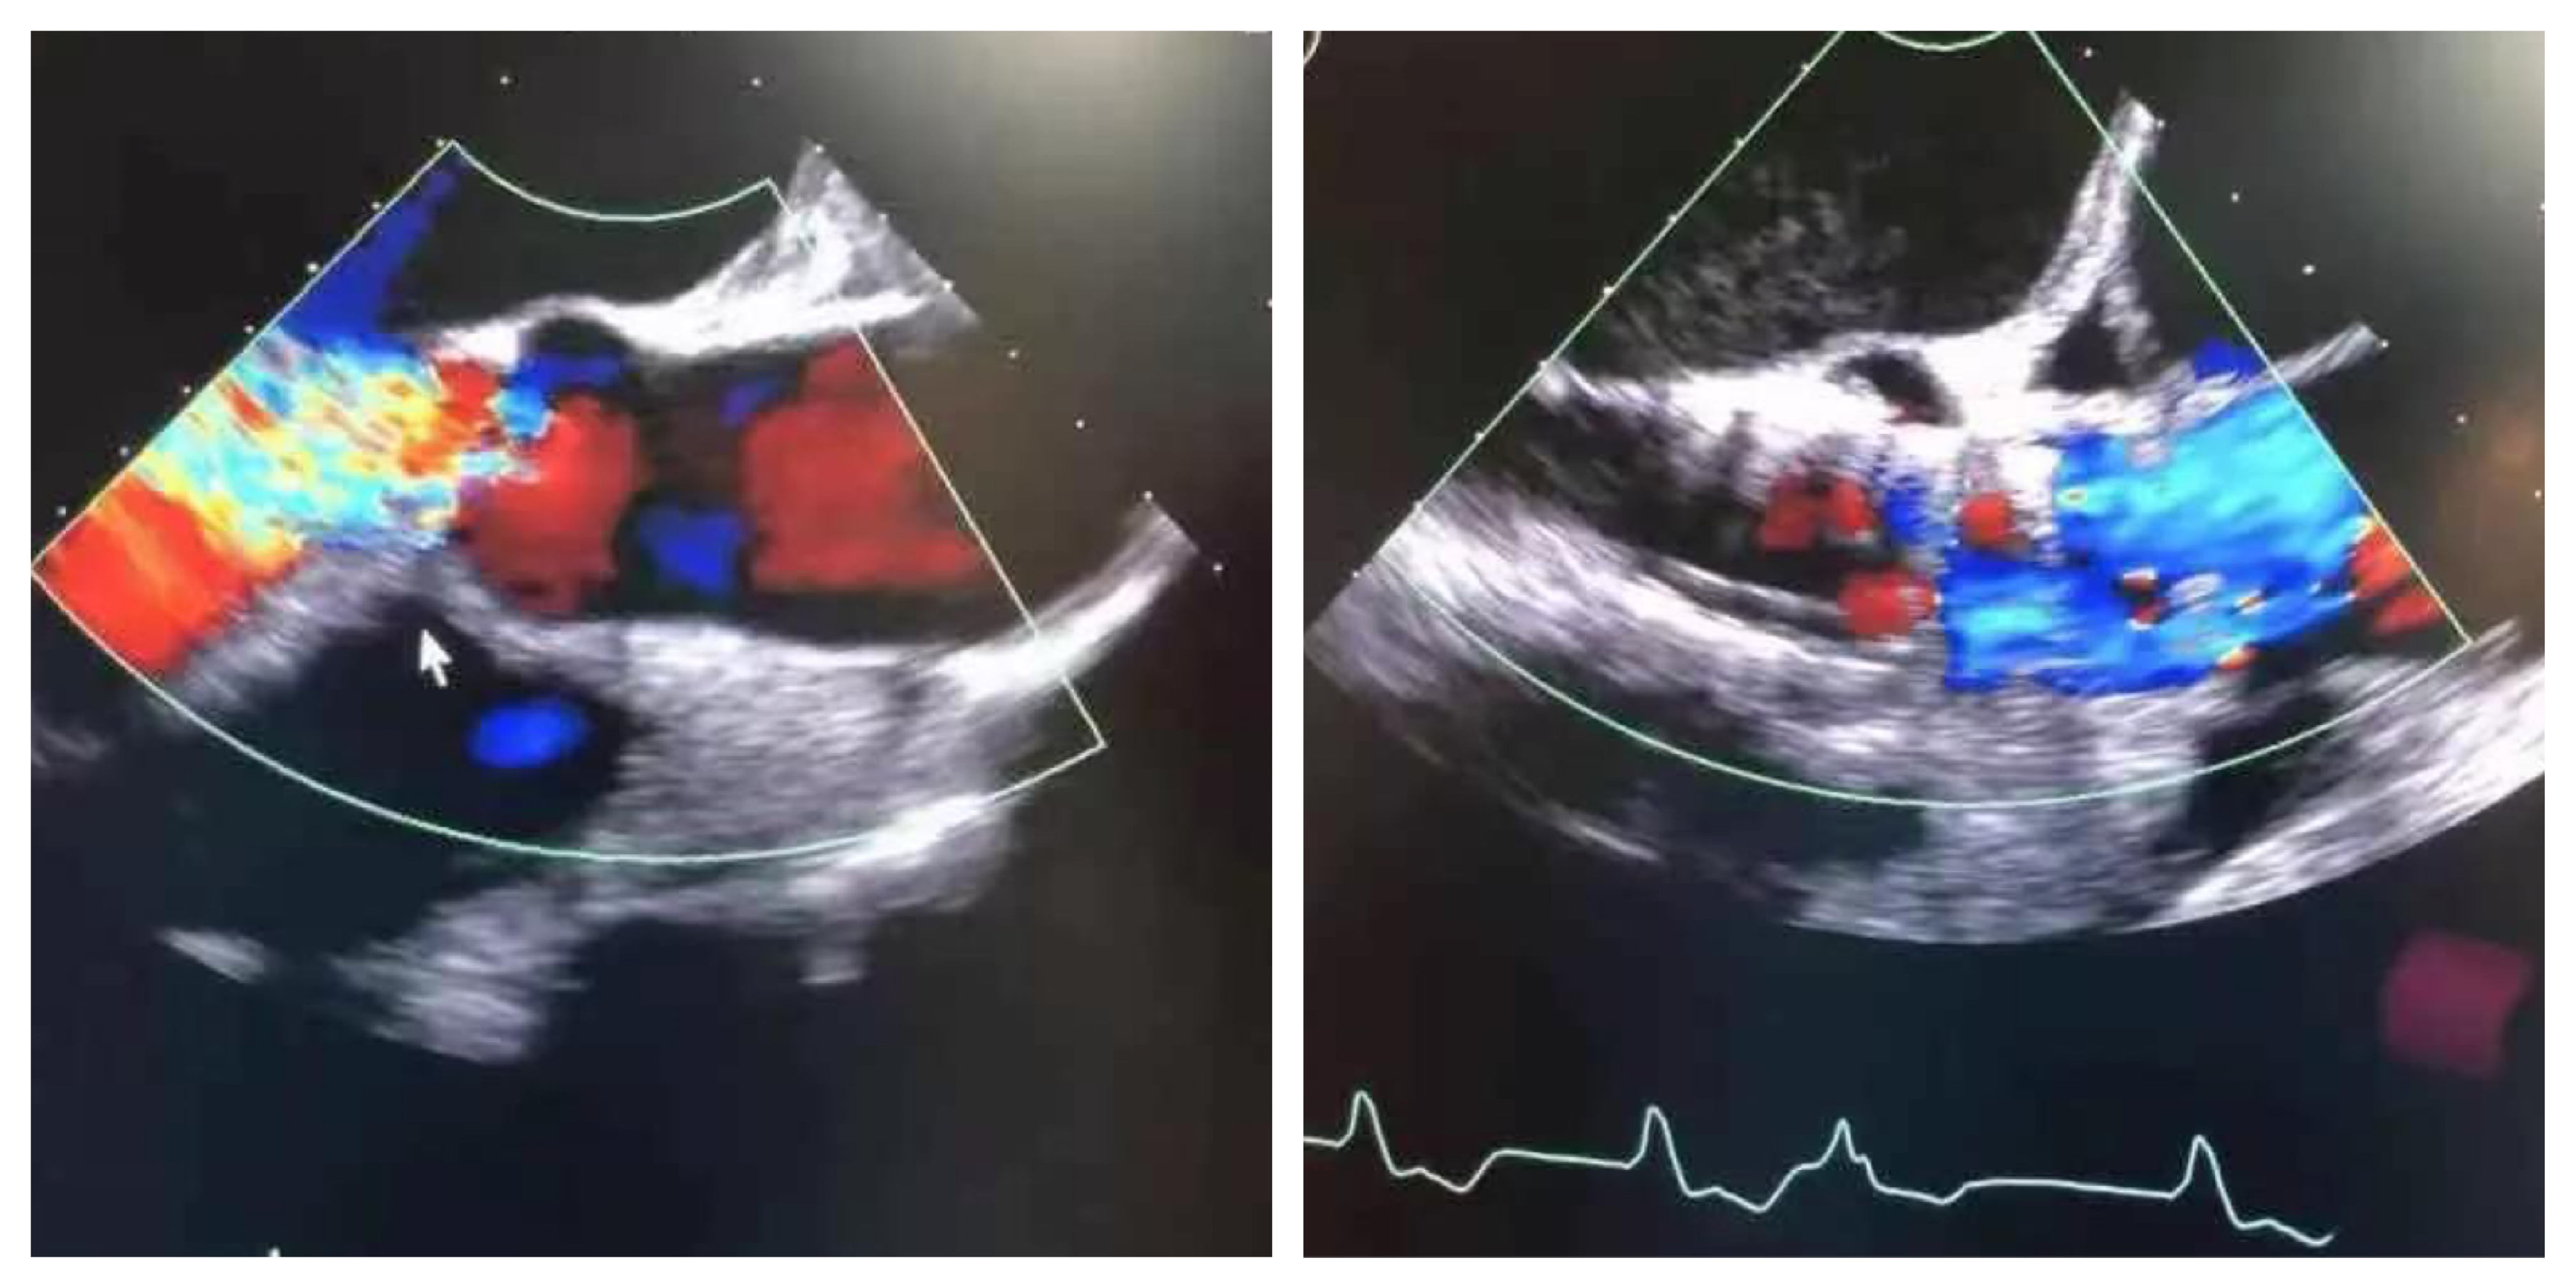

术后即刻:微量瓣周漏,舒张压明显改善至69mmHg。

术前心超 术后心超